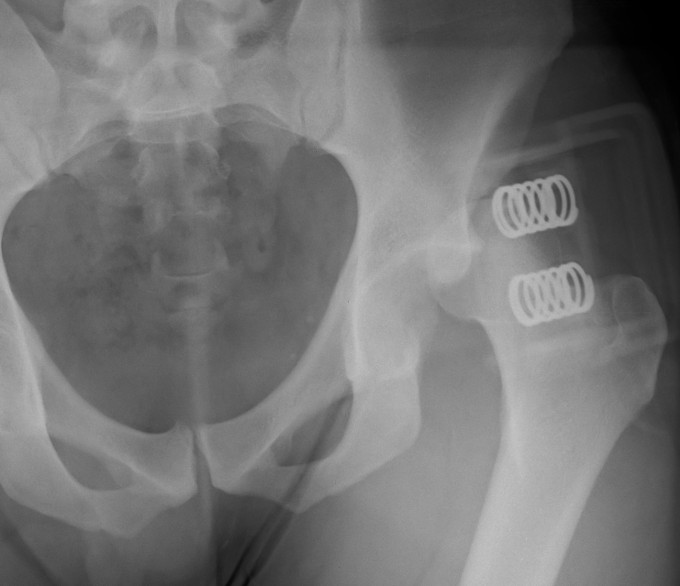

Posterior dislocation

- leg shortened, flexed, adducted & internally rotated

- head small on xray

Closed Reduction Posterior Dislocation

Technique

Full muscle paralysis on radiolucent table

- supine

- assistant places downward pressure on ASIS

- operator up on bed grasping leg

- flex hip to 90o, flex knee to 90o

Technique

- ER head around acetabulum / axial traction or

- IR head around acetabulum / axial traction

Post reduction

- check concentric reduction on II

- check stability in flexion

Unstable reduction

- skeletal traction / femoral steinman pin